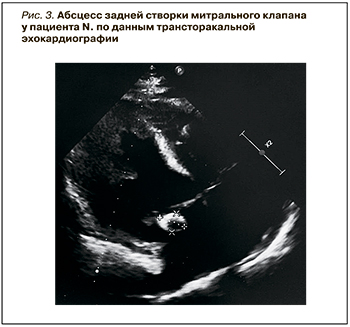

На 20-й день у пациента были отмечены рецидив лихорадки до 37,5 °С и повышение уровня воспалительных маркеров (табл.). После выполнения ПЦР-теста на COVID-19, который оказался положительным, к лечению был добавлен ремдесвир 100 мг/сут. При ЭхоКГ, проведенной на 24-й день, в основании задней створки митрального клапана определялась гиперэхогенная структура с анэхогенным центром d=1,85 х 1,37 см, предположительно указывавшая на абсцесс створки клапана (рис. 3).

На фоне присоединения коронавирусной инфекции в течение нескольких дней у пациента наблюдалось нарастание тревоги, появление психомоторного возбуждения и агрессии. По результатам консультации психиатра были диагностированы органическое тревожное расстройство, органическое заболевание головного мозга сложного генеза. На 31-й день при контрольной ЭхоКГ существенной динамики данных не наблюдалось. Пациент подписал отказ от госпитализации и был выписан на амбулаторный этап с рекомендациями.

По данным контрольной ЭхоКГ, размеры абсцесса задней створки митрального клапана остались прежними. Кардиохирургом было рекомендовано оперативное лечение (показания – внутрисердечный абсцесс, эмболия сосудов мозга), от которого пациент категорически отказался. При очередном лабораторном контроле отмечалось дальнейшее снижение маркеров системной воспалительной реакции (см. табл.).